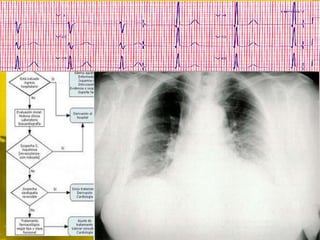

 A. inicial: perfil cardiológico

 ECG

 Rx torax

- Solicitar ECO ambulatoria

- Espirometría para diagnóstico diferencial

- En caso de presencia de síntomas iniciar

• 68.

 A. inicial:perfil cardiológico  ECG  Rx torax

• 69.

- Solicitar ECOambulatoria - Espirometría para diagnóstico diferencial - En caso de presencia de síntomas iniciar tratamiento